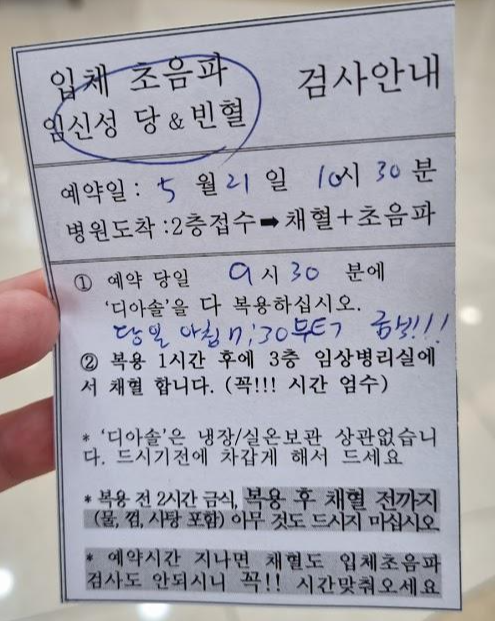

드디어 대망의 임당 검사(임신성 당뇨 검사)가 있어 미리

디아솔 에스와 안내문을 받았어요!

검사 전 금식이라니 벌써 긴장되네요.